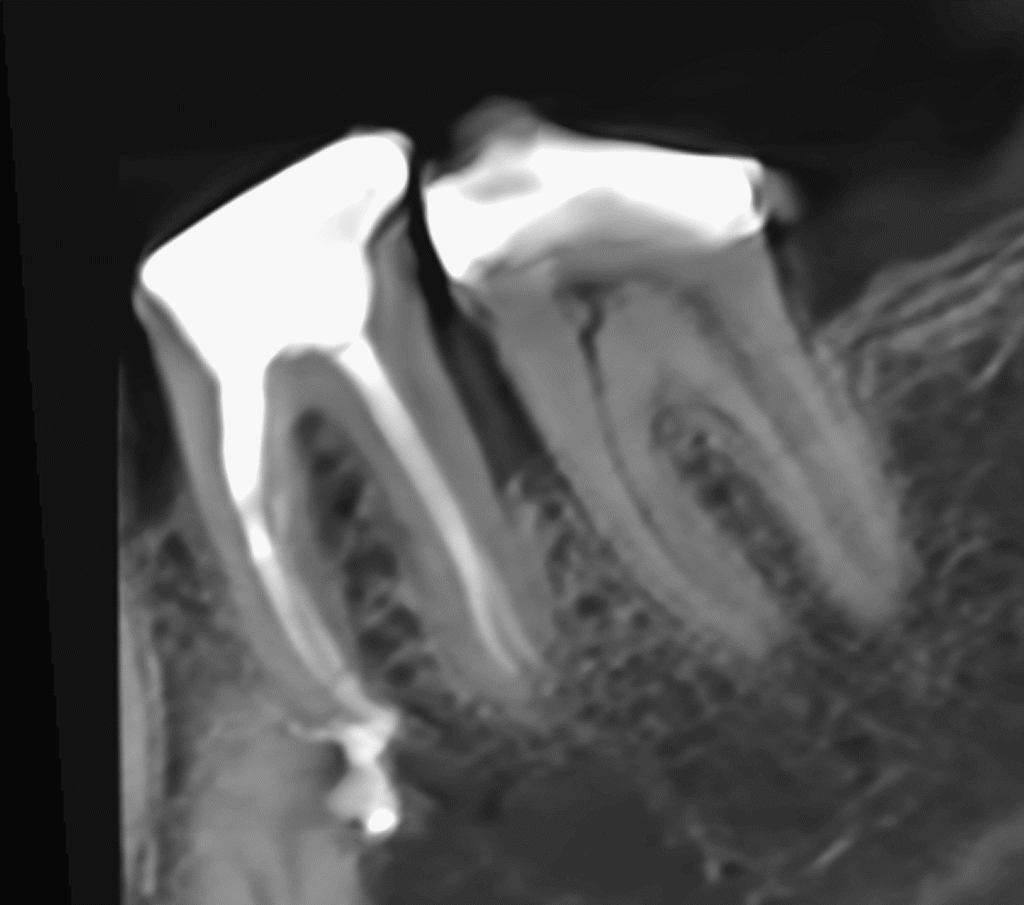

Pacjentka lat 54 trafiła do mojej kliniki skierowana z innego gabinetu celem leczenia endodontycznego zęba 46. W badaniu stwierdziłem znaczny zanik światła kanału korzeniowego. W badaniu tomograficznym stwierdziłem całkowity zanik kanału korzeniowego w strefie mezjalnej. Korzeń dystalny mimo widocznego światła kanału na CBCT, widoczne było wiele zwapnień w środkowej części kanału. Po wykonaniu dostępu endodontycznego zlokalizowałem materiał wypełniający kanał pozostawiony po poprzednim nieskutecznym leczeniu endodontycznym. Do usunięcia wykorzystałem laser 2780nm (25mJ/puls). W kolejnych etapach instrumentacji wspomaganie ultradźwiękami oczyściłem strefy mezjalną i dystalną. Instrumentacja themo-

mechaniczna polegała na zastosowaniu protokołu ciągłej chelacji wraz z użyciem lasera

2780nm z końcówką płaską (50mJ/puls) celem udrożnienia przestrzeni endodontycznych. Po wstępnym uzyskaniu drożności zastosowałem instrumentację maszynową wspomagająco celem udrożnienia przestrzeni. Finalnie obturacja z zastosowaniem ćwieków gutaperkowych kalibrowanych na WL i uszczelniacza na bazie krzemianów wapnia. W przeciwieństwie do tradycyjnych uszczelniaczy, nie wymaga mieszania, co eliminuje błędy w proporcjach i zapewnia powtarzalną konsystencję. Jest materiałem wysoce biokompatybilnym i bioaktywnym. Finalnie zamknięto ząb odbudową kompozytową tymczasową i skierowano na dalsze leczenie protetyczne do gabinetu kierującego pacjenta.